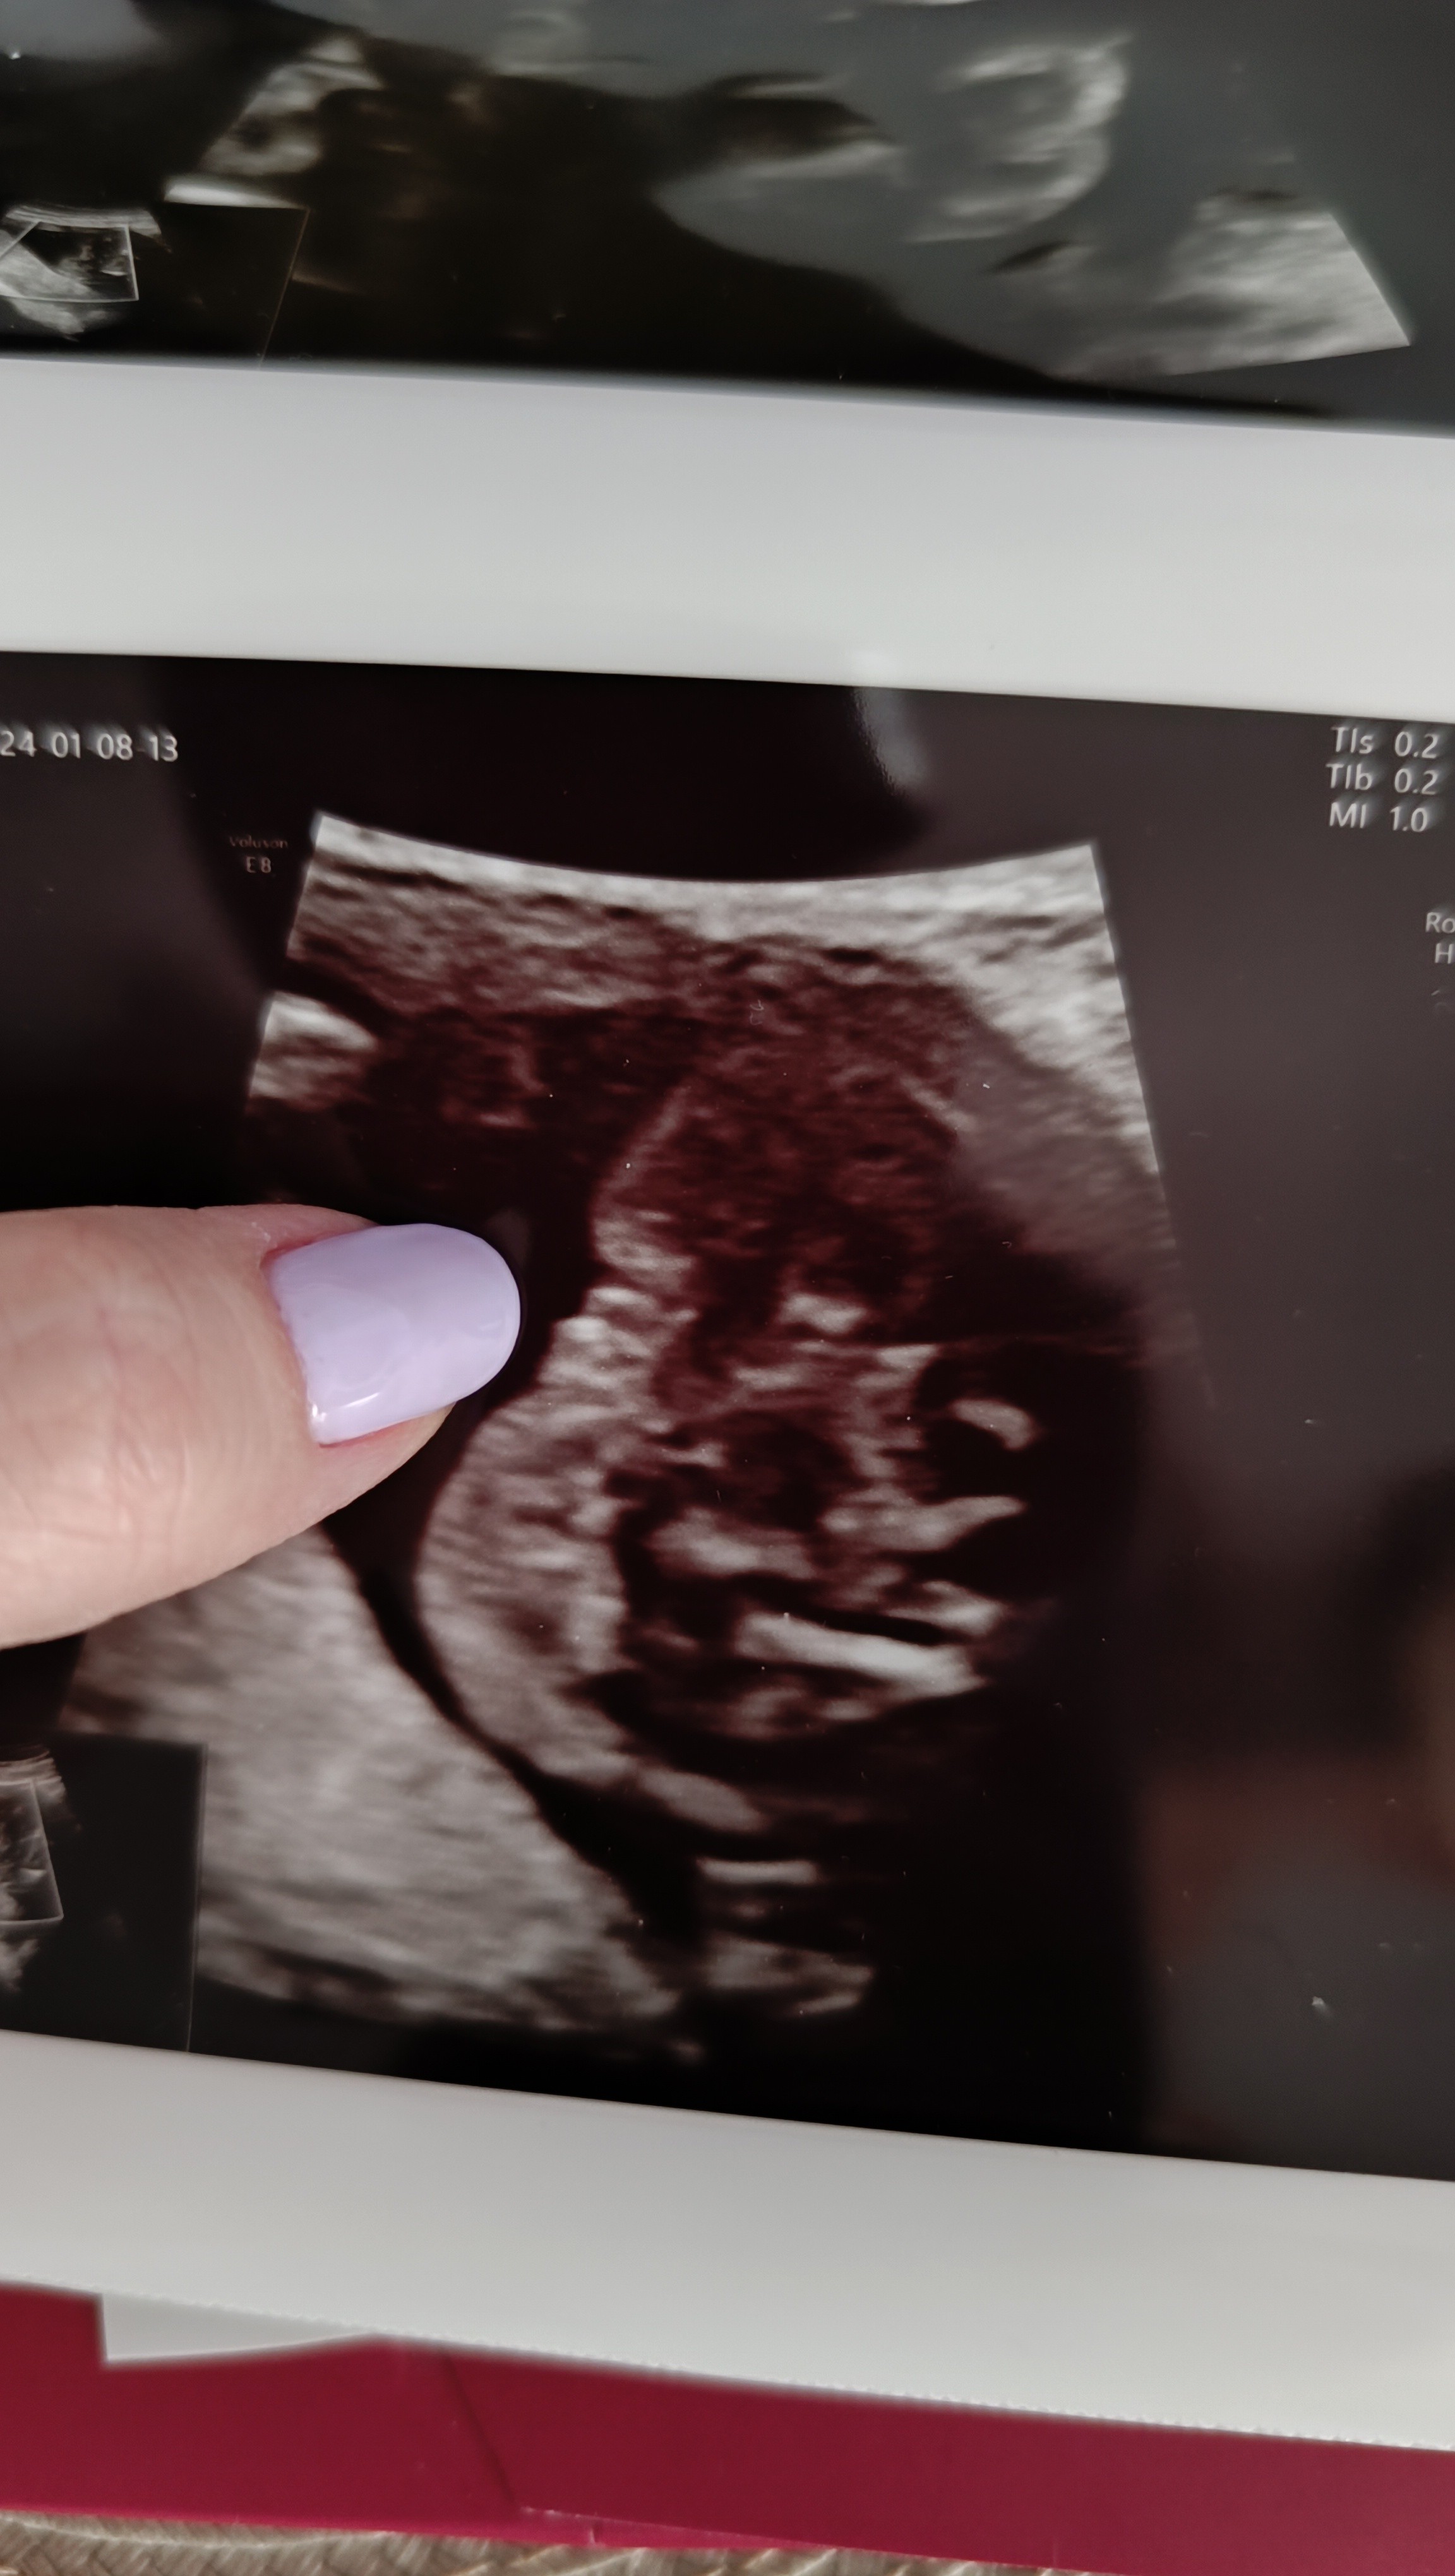

A jaka płeć u mnie widzicie ? Ja słyszałam, że może się rozejść na wargi sromowe właśnie

• Screenshot_20240106_152934_Messenger.jpg

Screenshot_20240106_152934_Messenger.jpg

277,3 KB · Wyświetleń: 131